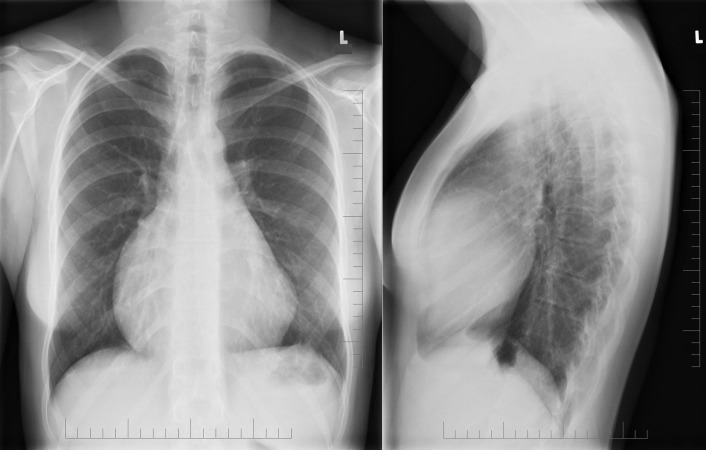

Ebstein’s anomaly. Note the moderate cardiomegaly, the prominence of the right atrium and right ventricle as well as the small main pulmonary artery.